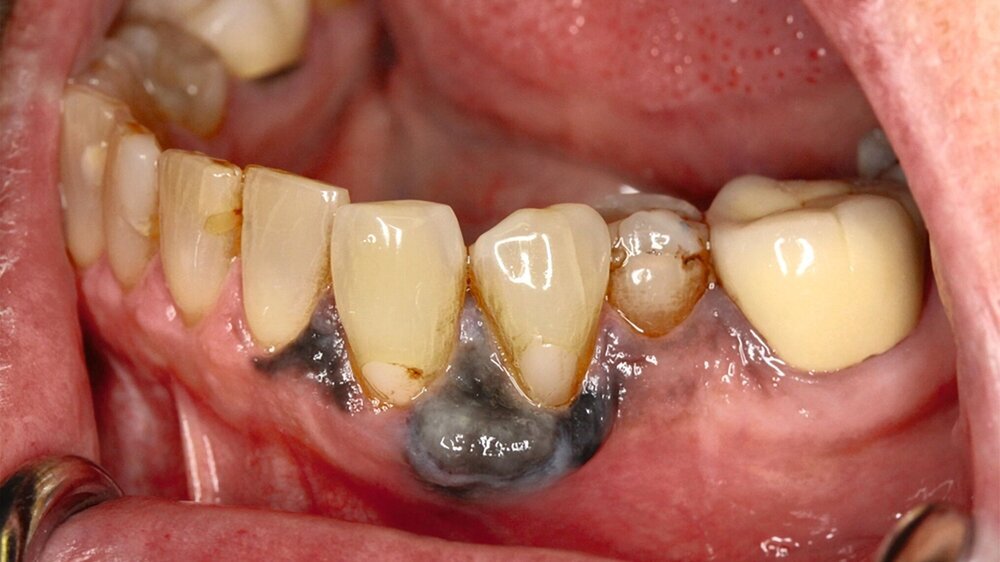

Eine im Januar 2024 alio loco durchgeführte Probenentnahme ergab eine resorptive Entzündung mit Pigmenteinlagerungen. Die Patientin berichtet, dass die Schleimhautveränderung etwa vier Wochen vor der Vorstellung bei uns begonnen habe zu wuchern. Klinisch zeigte sich eine 10 mm x 7 mm messende, exophytisch wachsende, schwarz pigmentierte Raumforderung (Abbildungen 1 und 2). Durch eine Probenentnahme in domo konnte histopathologisch ein malignes Melanom gesichert werden.